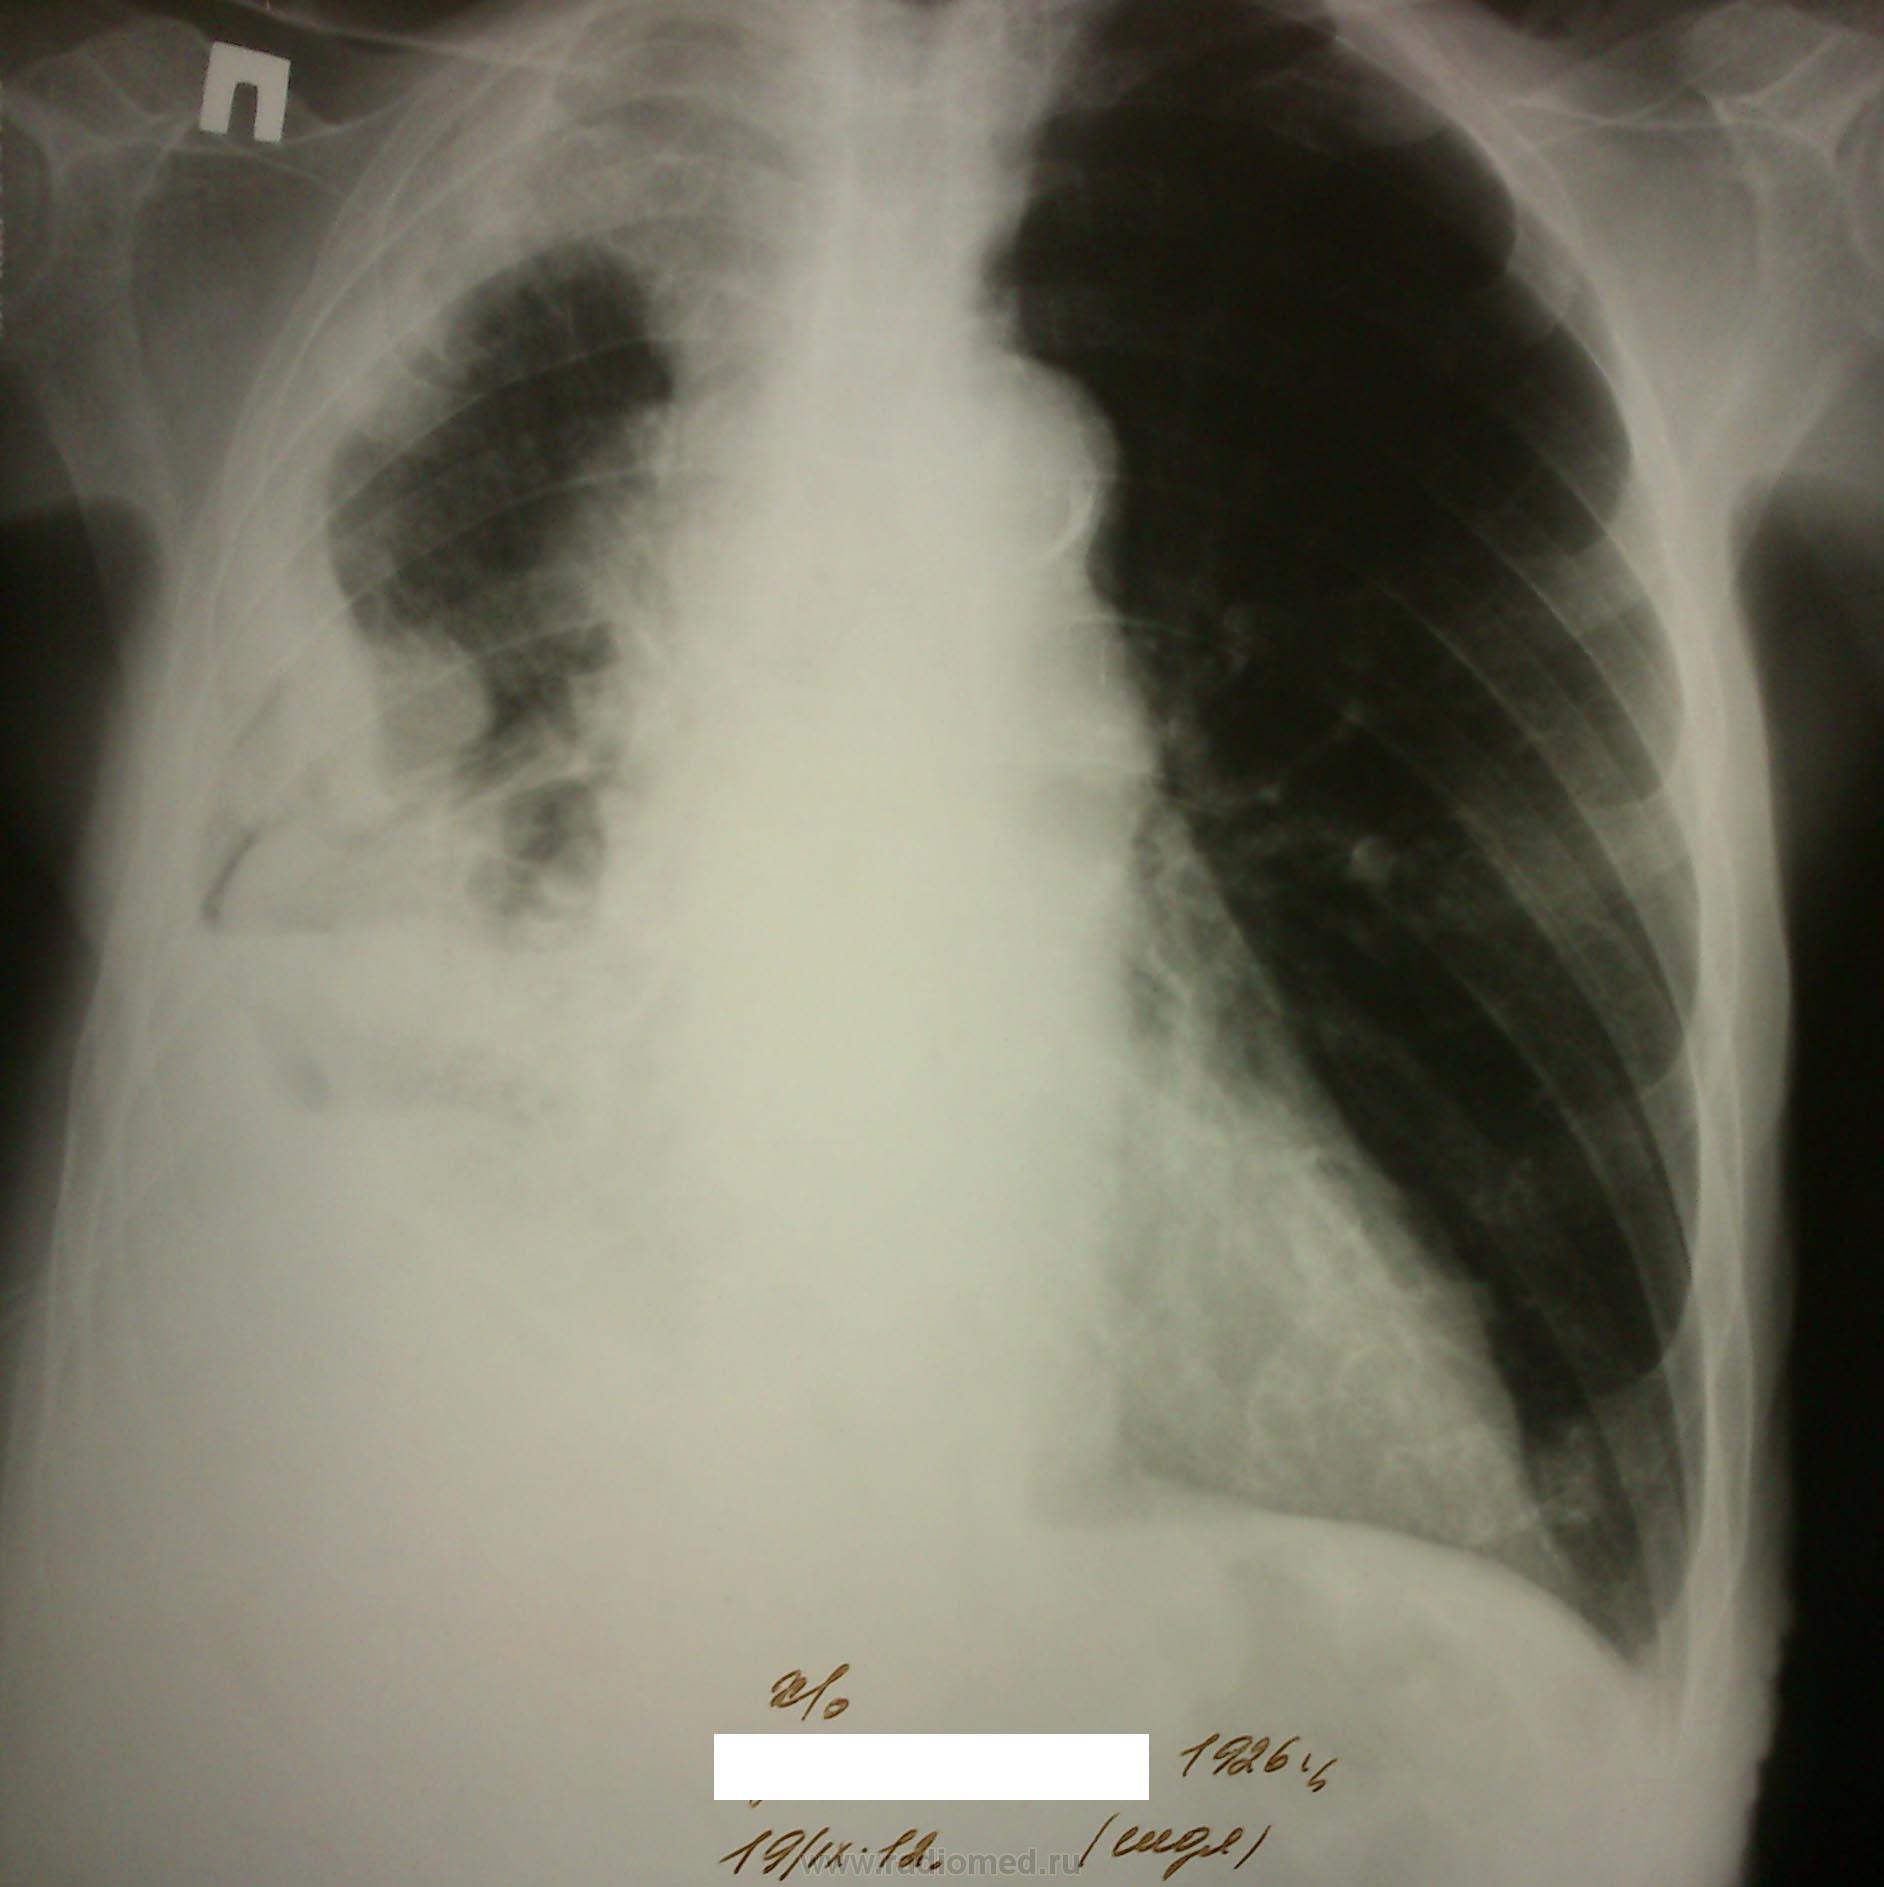

После плевральной пункции проведено контрольное рентгенологическое обследование.

Не могу разобраться, что за уровни жидкости на рентгенограммах при контрольном исследовании, возможно жидкость между плевральными спайками? Какова природа гидроторакса? Очень интересно ваше мнение…

2. после пункции

Мне тоже не ясно это за полость, вопрос с образованием решен, но что за уровни жидкости?

Развитие пневмогидроторакса после плевральной пункции, на фоне спаечного процесса?

Оно самое.